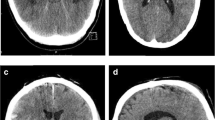

Five patients were implanted with a 2.8-mm EVD catheter (VentriGuard®, Neuromedex, Hamburg, Germany) and seven patients with a 2.5-mm catheter (Ventricular Catheter, Christoph Miethke, Potsdam, Germany) with a mean operating time of 25.75 min (+ / − 14.97 min; range, 10–40) including patient positioning, sterile table setup, preparation and draping in sterile fashion, and cleanup. All catheters were successfully placed at the first puncture attempt. None of the patients showed incorrect catheter placement evaluated with the GAVCA grading score. Eight patients showed optimal (grade I), and four patients showed intermediate catheter positions (grade II), while no grade III or IV catheter positions were observed. Anatomically, ten catheters were placed in the ipsilateral ventricle, and two had their tips in the third ventricle, while perforation holes showed entirely intraventricular location. The selection of the catheter’s outer diameter showed impact on the quality of catheter positions. After switching to the smaller catheter diameter, all catheters showed an optimal position in the postoperative scans (Fig. 3). During follow-up, two EVDs were converted into a ventriculoperitoneal shunt. Due to elevated CSF cell count and lactate values on postoperative day 5 without pathogen detection, antibiotic treatment was required before shunt insertion was done one week afterwards. Another patient had subdural hematoma with a thickness of 8 mm without necessity of intervention, and one EVD catheter was dislocated during transport from the ICU to the CT scanner on day five after implantation (Table 3).

In terms of technical considerations, we experienced some pearls and pitfalls, which are additionally worth mentioning. Since the planning of the entry point must be done from the scalp instead of the bony skull surface, as described previously for the operating room setting, adaptation especially in the coronal CT/MRI imaging is necessary to delineate the contrast of the skin surface for the virtual planning procedure. In the bedside setup, placing the ventricular catheter guide onto the relatively flexible scalp surface is a bit more susceptible to instability. Special care must be taken before starting to drill, as one hand has to remain solidly on the catheter guide until the burr hole is safely completed. Careful adjustment of an anti-plunge drill stop and strict maintenance of sterile conditions should be guaranteed to minimize intracranial hematoma and CSF infection as possible complications. In this study, only electric single-use power drills with a diameter of 2.7 mm were available, which lead to problems with the insertion of standard 2.8-mm EVD catheters (VentriGuard®, Neuromedex, Hamburg, Germany), as they tend to pass the burr hole only with increased physical effort. In the further course of the learning curve, a modification to a 2.5-mm diameter ventricular catheter (Ventricular Catheter, Christoph Miethke, Potsdam, Germany) was performed after the first five patients, which smoothened the procedure relevantly and lead to faster and better placement accuracy.